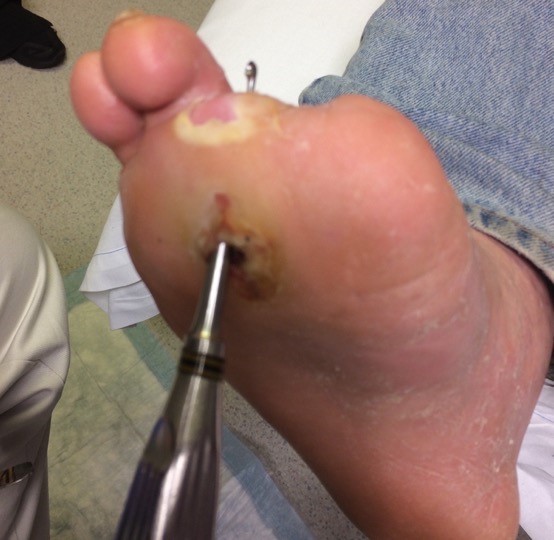

Wounds that are chronic, large, deep, or overlie a bony prominence are at high risk for underlying bone infection. The presence of a 'sausage toe' (Figure 11) or visible bone is highly indicative of osteomyelitis.[47]

-

Probe-to-bone testing: In patients with suspected CLTI who have a foot ulcer, clinical guidelines recommend a probe-to-bone test to assess depth and the probability of underlying osteomyelitis.[5]

Probe-to-bone test: gently probe the ulcer with a sterile blunt metal probe (Figure 12). If the metal strikes bone (detected by its hard, gritty feel) in a patient at high risk for osteomyelitis, there is a high likelihood that the patient has osteomyelitis. In practice, for all open AUs with positive probe-to-bone test, clinicians might opt for further imaging to assess for osteomyelitis (e.g., magnetic resonance imaging). See section 'Diagnosis' below

|

Fig. 11. Sausage toe suggestive of osteomyelitis [54]

Fig. 12. Probe-to-bone in a DFU